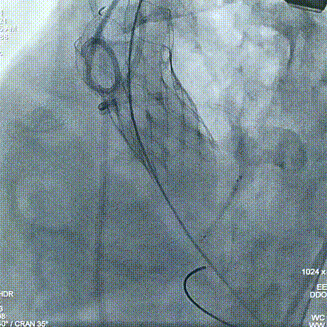

术中操作

球囊预扩

瓣膜定位

经评估后植入左主干烟囱支架